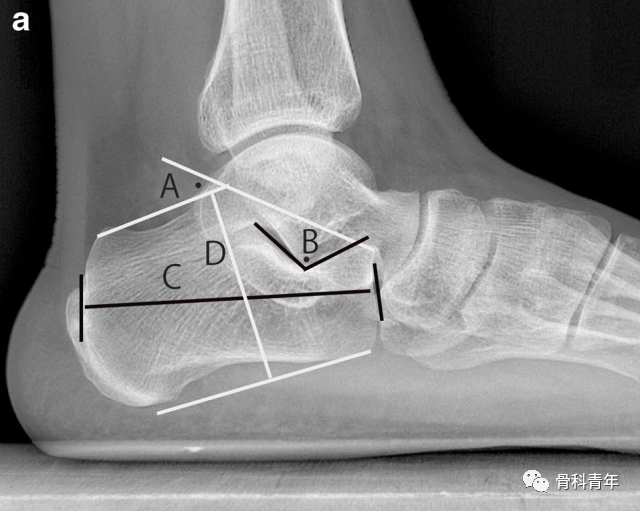

正常跟骨解剖参数的测量方法。A:Bohler’s角;B:Gissane’s角;C:跟骨长度;D:跟骨高度;E:跟骨宽度。